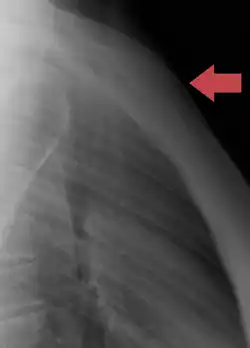

Sternum, lateral aspect -